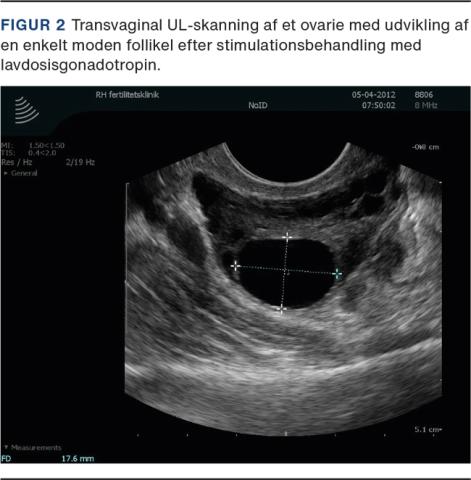

Ved direkte stimulation af ovarierne anvendes injektionsbehandling med gonadotropiner [14]. Behandlingen kan være en klinisk udfordring pga. den øgede risiko for hyperrespons hos kvinder med PCOS (Figur 3), og follikeludviklingen skal monitoreres tæt. Der gives en lav dosis gonadotropin fra cyklusdag 2-5, og kvinden ses til kontrol efter ca. syv dage og derefter ved behov, indtil der ses modning af en enkelt follikel. Ved amenoré og smalt endometrium kan stimulationsbehandlingen påbegyndes på en vilkårlig dag. Når der ses en follikel på 17 mm i diameter, induceres ovulation med hCG. Ved udvikling af to modne follikler bør patienten informeres om risikoen for flerfoldsgraviditet ved IUI. Ved udvikling af tre follikler ≥ 14 mm i diameter kan behandlingen overvejes aflyst eller konverteret til in vitro-fertilisering (IVF). Ved udvikling af mere end tre follikler ≥ 14 mm i diameter skal cyklus aflyses eller konverteres til IVF. Kvinder med PCOS-relateret infertilitet har generelt gode chancer for at opnå graviditet, når en ovulatorisk cyklus er etableret [15]. Der er rapporteret om kumulative graviditetsrater på op til 78% og en samtidig lav forekomst af flerfoldsgraviditeter (< 3%) og hyperrespons efter ovulationsinduktion med lavdosisgonadotropinstimulation [16].